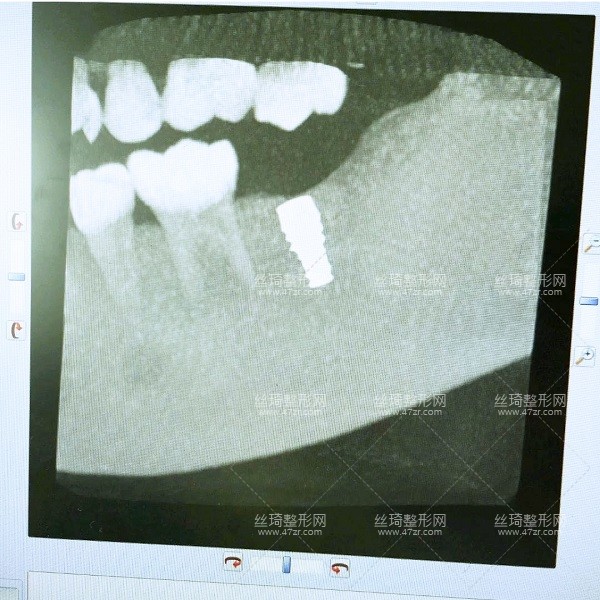

2.種植牙案例

手術(shù)第1天

一直不知道什么原因?qū)е挛业难罆@樣,多方咨詢之后選擇了長沙中諾口腔進(jìn)行整牙,過去檢查了一下,醫(yī)生說我可以搞種植牙,但是以前補(bǔ)過的牙現(xiàn)在顏色變了,需要重新做,看來是個大工程啊,啊啊啊啊~~~

手術(shù)第2天

今天過來醫(yī)生檢查了我的牙床和骨組織,情況不錯,可以直接調(diào)節(jié)。首先助理幫我清潔口腔,護(hù)士準(zhǔn)備手術(shù)室,清理過口腔后,吃了止痛藥,然后進(jìn)手術(shù)室,然后躺到牙椅上,就打麻藥的時候有點(diǎn)緊張,種牙很輕松,全程一個半小時。出來后,冰敷了,告訴我注意事項(xiàng),讓我一周后來拆線。